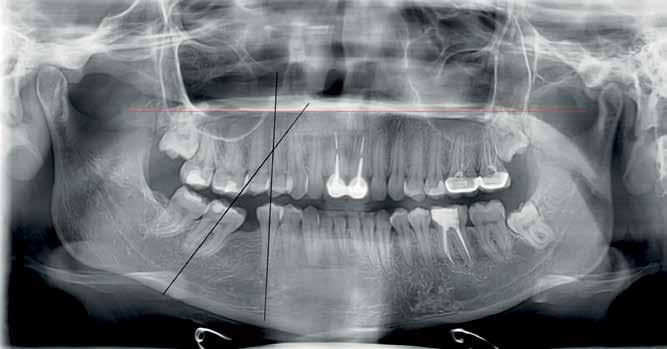

A panoramic x-ray showed the absence of the right first mandibular molar, a 45 degrees inclination of the second and third mandibular right molars, a vertical bone defect at the old extraction site, with a large composite filling on a endodontically treated mandibular left first molar.

Non extraction treatment, with mesial root movement and protraction of the mandibular second and third molars in order to close the residual space, create a solid contact between the mandibular second molar and second premolar without the need for prosthetic dental implant or crown. This option would require longer orthodontic treatment time with extensive follow up visits, however no extra cost is allocated for surgical and prosthetic procedures. (Figures 1 and 2)

Figure 1 Figure 2